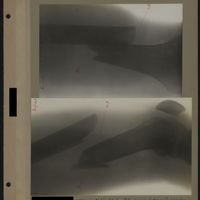

0064 - Page 60 - [Radiographies de l'abdomen]0064 - Page 60 - [Radiographies de l'abdomen]